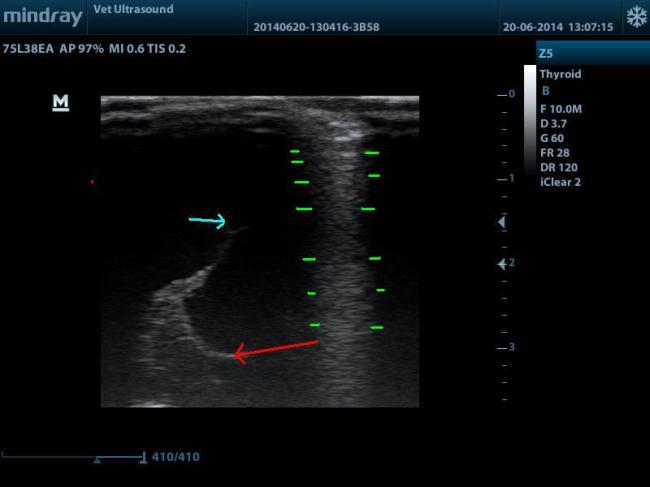

Η ΠΡΩΤΗ ΕΙΚΟΝΑ ΠΟΥ ΠΗΡΑ ΑΠΟ ΤΟΝ ΥΠΕΡΗΧΟ. ΟΙ ΔΥΟ ΠΡΑΣΙΝΕΣ ΓΡΑΜΜΕΣ ΟΡΙΟΘΕΤΟΥΝ ΤΗΝ ΠΕΡΙΟΧΗ ΑΠΟ ΤΟ ΥΠΟΛΟΙΠΟΜΕΝΟ ΕΓΚΕΦΑΛΙΚΟ ΠΑΡΕΓΧΥΜΑ. ΥΠΗΡΧΕ ΟΜΩΣ Η ΥΠΟΨΙΑ ΥΔΡΑΝΕΓΚΕΦΑΛΙΑΣ.

ΣΤΗΝ ΕΙΚΟΝΑ ΑΥΤΗ ΒΛΕΠΟΥΜΕ ΤΗΝ ΔΙΑΤΑΣΗ ΤΗΣ 3ΗΣ ΚΟΙΛΙΑΣ ( ΜΠΛΕ ΒΕΛΟΣ ), ΔΙΕΝΓΚΕΦΑΛΟΣ ( ΚΟΚΚΙΝΟ ΒΕΛΟΣ ), ΟΙ ΠΑΥΛΕΣ ΑΦΟΡΙΖΟΥΝ ΤΟ REVERBERATION ARTIFACT ΠΟΥ ΔΗΜΙΟΥΡΓΕΙΤΑΙ ΛΟΓΩ ΜΗ ΚΑΛΗΣ ΕΠΑΦΗΣ ΤΟΥ ΗΧΟΒΟΛΕΑ ΜΕ ΤΟΝ ΑΣΘΕΝΗ.